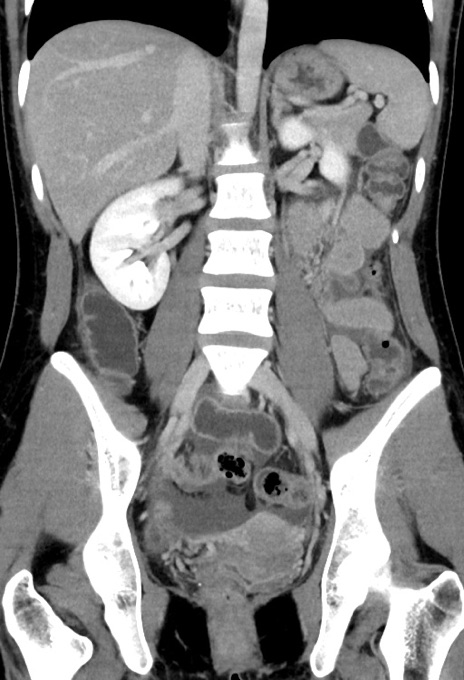

症例17(冠状断像)

【症例】20歳代女性

【主訴】嘔吐、下腹部痛

【現病歴】昨日夕食後に嘔吐し下腹部痛が出現。本日になっても嘔吐持続し改善しないため来院。

【身体所見】意識清明、BT 37.2℃、BP 108/67mmHg、腹部:平坦、やや硬、下腹部正中から右にかけて圧痛あり、反跳痛軽度あり、tapping pain(+)。

【データ】WBC 13600、CRP 14.94

横断像